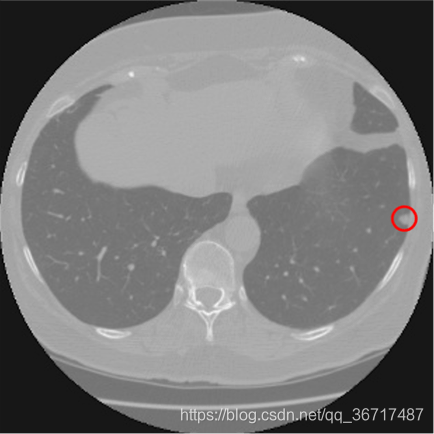

找到疑似肺结节后,可以使用常见的图像分类算法(如CNN等)对疑似肺结节进行分类,得出疑似肺结节是否为真正肺结节的概率。下图是找到的肺结节例子。